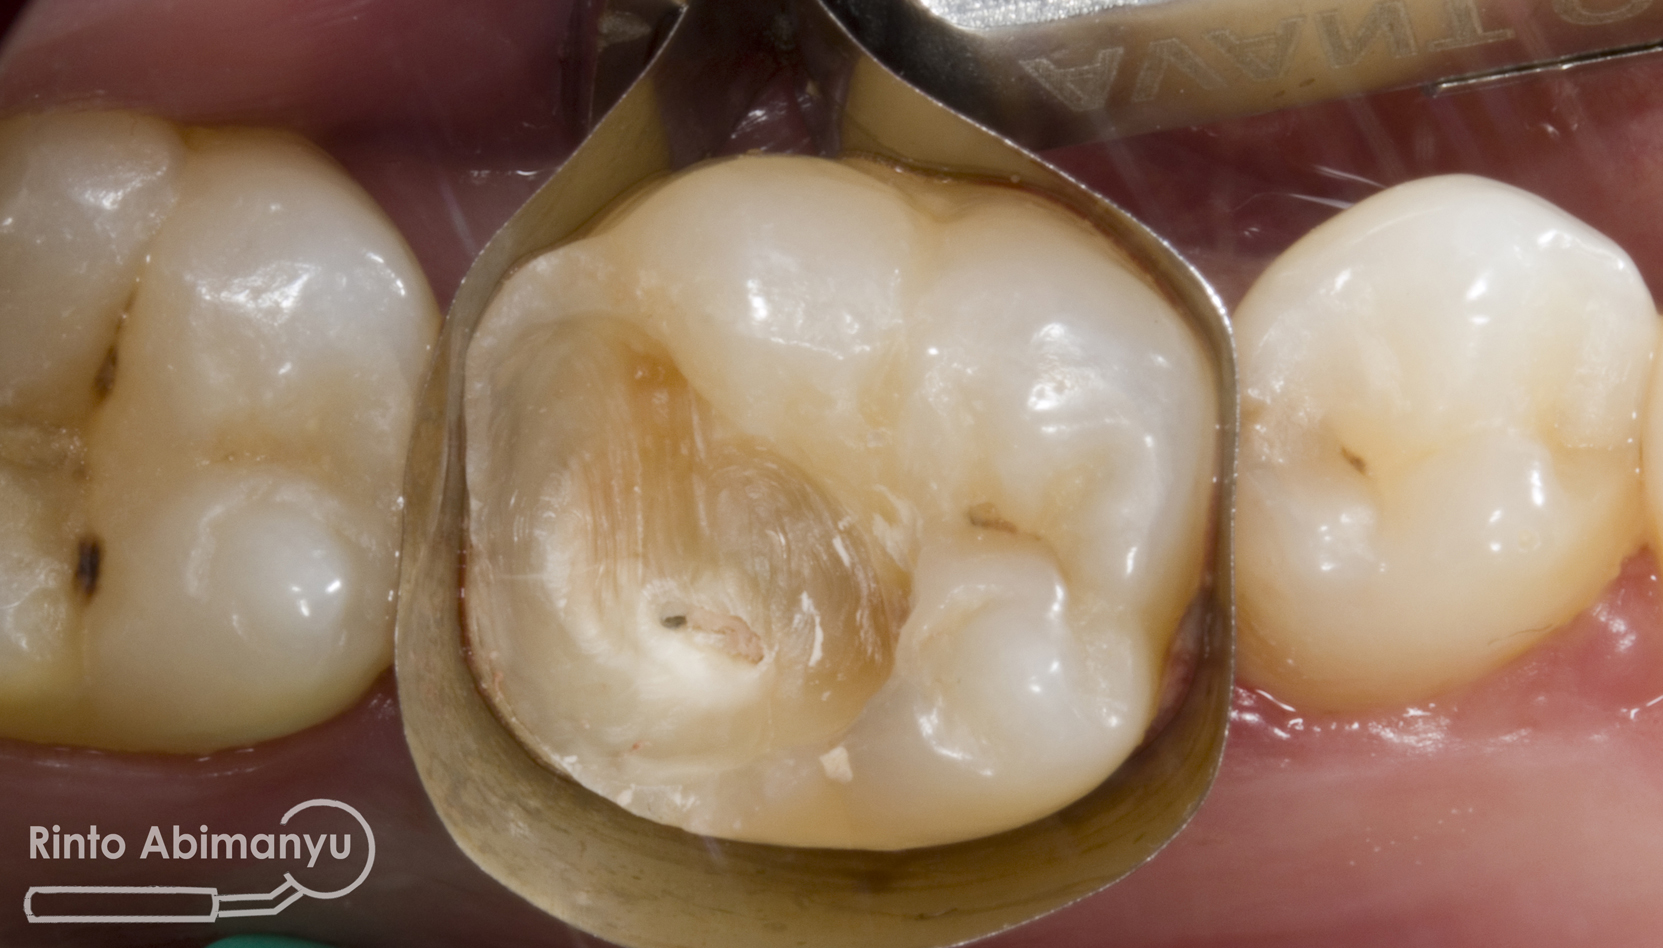

Seluruh jaringan karies dibuang menggunakan bur tungsten carbide low speed, dilanjutkan pembuatan artificial wall menggunakan komposit dengan bantuan matriks greatercurve.